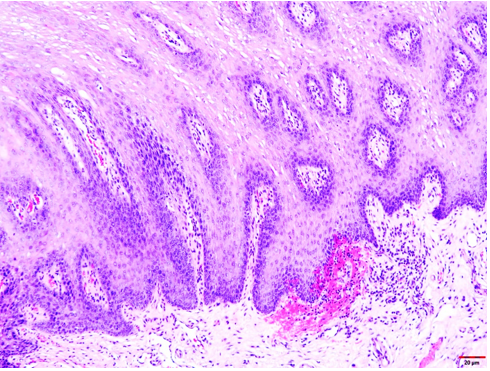

The formalin-fixed tissue specimen was subjected to routine processing after which 5μm sections were cut and stained with hematoxylin and eosin. The tissue sections showed hyperkeratinized surface mucosal epithelium supported by lamina propria (Figure 4). The epithelium was covered by a thick layer of parakeratin. The spinous cell layer was thickened and showed superficial layers of cells exhibiting prominent deeply chromatic nuclei surrounded by vacuolated cytoplasm imparting optically clear cells (Figure 5). The basal and suprabasal layers of cells exhibited the normal cellular maturation pattern without any cellular or nuclear atypia (Figure 6). Subepithelial inflammatory cell infiltrates were noted in the superficial lamina propria. A diagnosis of “Hyperparakeratosis with prominent perinuclear vacuolization of the epithelium”, consistent with Pachyonychia congenita was made.

Figure 5: Tissue section exhibiting the thickening of the spinous cell layer with superficial layers of cells exhibiting prominent deeply chromatic nuclei surrounded by vacuolated cytoplasm imparting optically clear cells